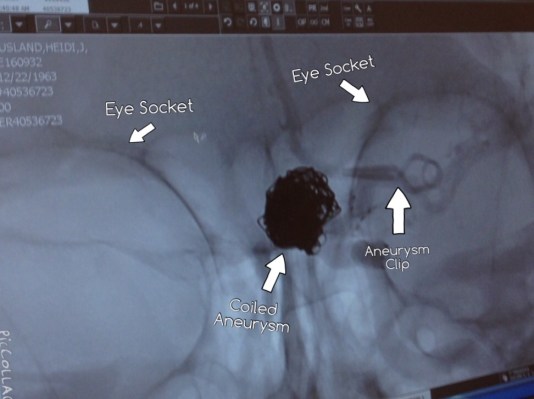

Brain Scan